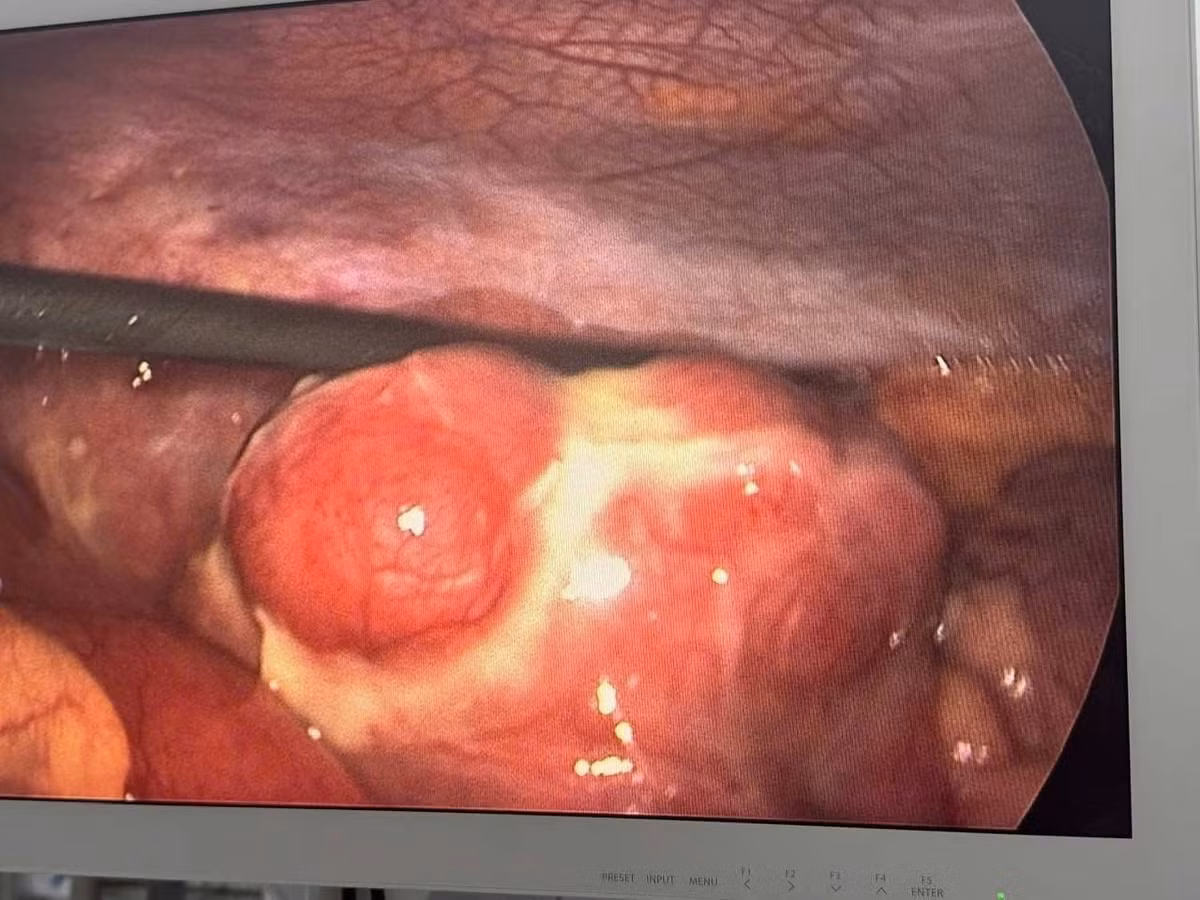

da-tui-thua-3.jpg

Hình ảnh đa túi thừa trên phẫu thuật nội soi - Ảnh BVCC